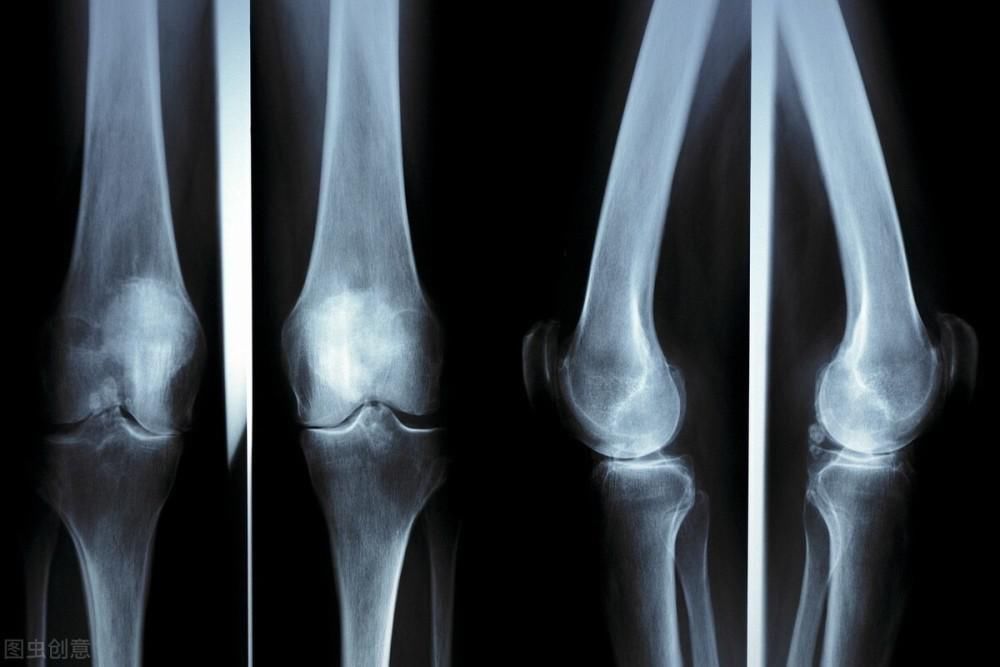

32岁的李女士是一名英语老师,几乎每年都是带毕业班,所以工作非常繁忙。除了日常授课之外,还要学习一些押题的小技巧,好帮助学生们学习英语,所以日常就靠浓咖啡来提神。周一的晚上,同学们把周末的作业都交了上来,李女士批改作业到10:00,和往常一样去倒了杯咖啡,然而膝盖疼痛难忍,小腿剧痛,他赶紧叫来保安将她送医院。医生诊断为李女士为骨质疏松性骨折,需要长期进行调理,所以接下来很长一段时间都不能继续进行教学,这不仅影响了李女士的日常生活,还对同学们的学习产生很大影响。

导致李女士骨质疏松的原因是什么呢?医生和李女士沟通后得知她长期喝浓咖啡,而这正是她出现骨质疏松的根源,因为咖啡因会抑制人体对于钙质的吸收,使得骨质变得非常脆弱,骨骼就不能很好的补充细胞和血液中的钙质。另外,林女士还经常熬夜加班,所以体内钙磷不均衡,更容易加快骨钙流失,才导致了最终产生骨质疏松性骨折。